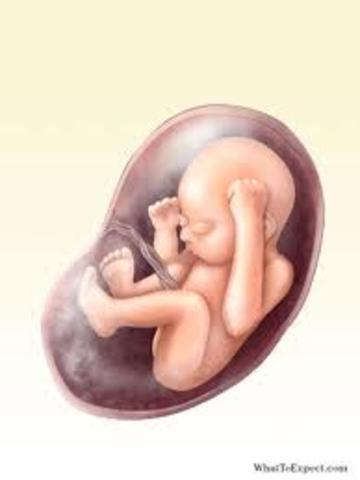

• Week 12

Week 12

By now, your baby weighs a full half-ounce and is about the size of a large plum. Most of his systems are in place, though there's still plenty of maturing to do. For one thing, his fetal digestive system is beginning to practice contraction movements necessary for eating, and his bone marrow is busy making white blood cells.